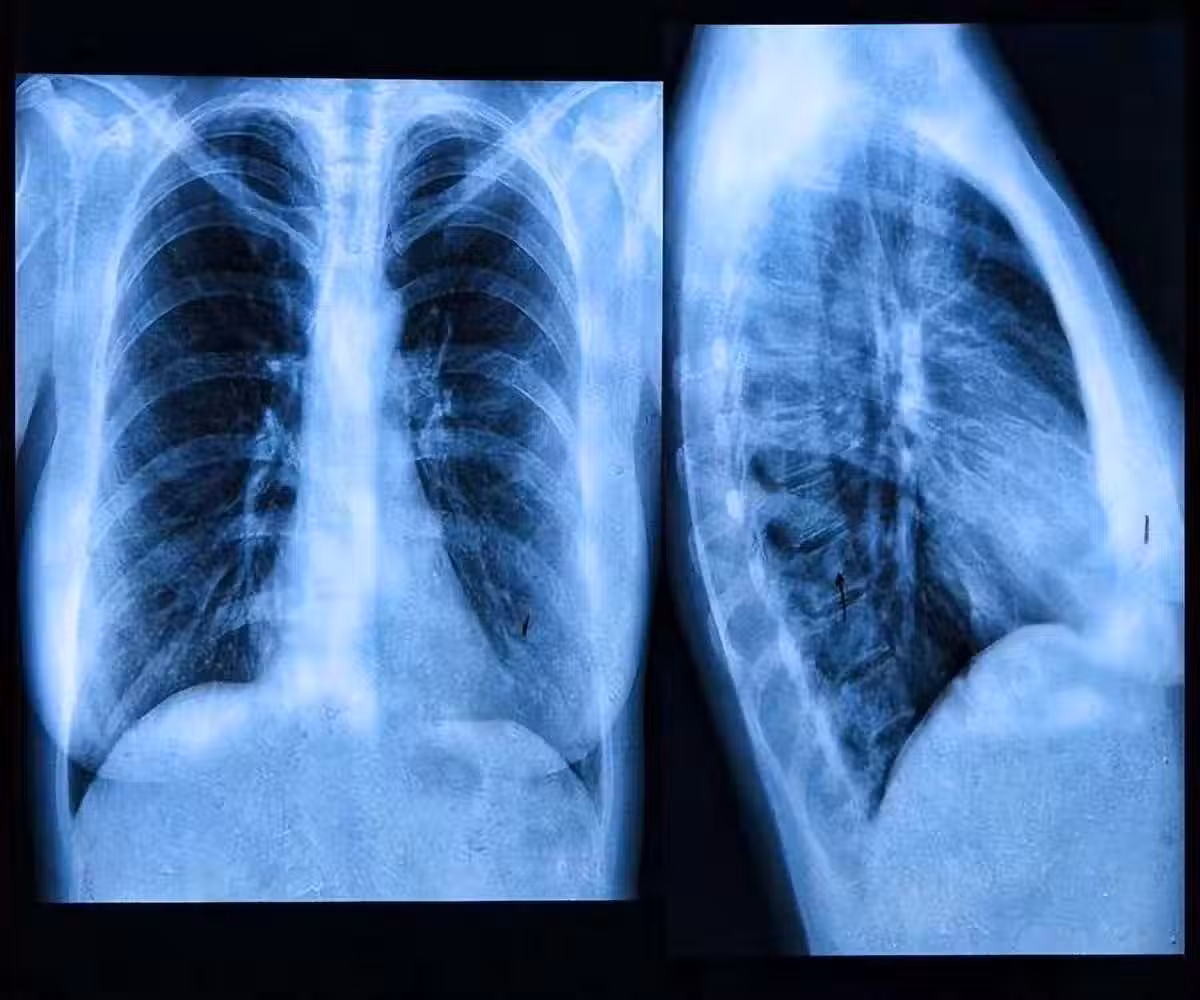

肺內有癌,腿疼告知?事實上,早期肺癌的5個跡象, 你更需要去關注

4、肺部持續疼痛

如果人的肺部持續疼痛,也有可能是肺癌造成的,隨著病情的發展,肺癌也會引起骨骼疼痛和肌肉疼痛。

這種痛感多發生在背部和肩部,運動程度越大,疼痛感也會有所增加。因此患上肺癌是禁止做任何劇烈運動的。